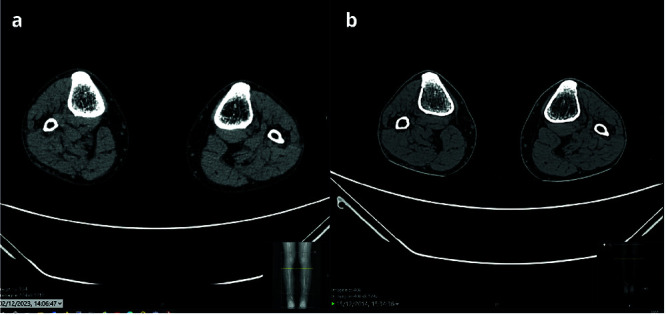

This case study examines the effectiveness of using combined CT imaging and 3D imaging in monitoring the prevention of sarcopenia through continuous daily exercises in an elderly patient. Using a 256-slice CT scanner with dose reduction technology and advanced muscle segmentation with the open-source software DAFNE, we compared changes in muscle mass and density in a 70-year-old patient in 2014 and in 2023. The obtained images allowed the creation of detailed 3D models for a more accurate and intuitive assessment of the leg musculature. Despite aging, the results of the scans performed at the beginning and end of the study period did not show significant changes in the patient's musculature, suggesting that a persistent Full-Body in-Bed Gym protocol ("Gym Bed" exercise routine) can effectively contribute to maintaining muscle mass and density in the elderly. These preliminary results highlight the potential of advanced imaging techniques not only to diagnose but also to quantify the effectiveness of non-pharmacological interventions against sarcopenia.

Abstract Image